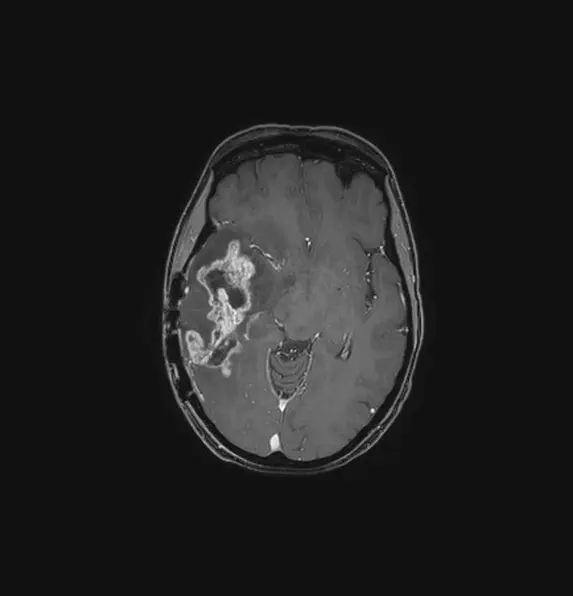

O diagnóstico começa com exames como ressonância magnética (RM) e tomografia computadorizada (TC), que fornecem imagens detalhadas do cérebro. A confirmação do tipo de tumor muitas vezes requer uma biópsia, onde uma amostra de tecido é retirada para análise.